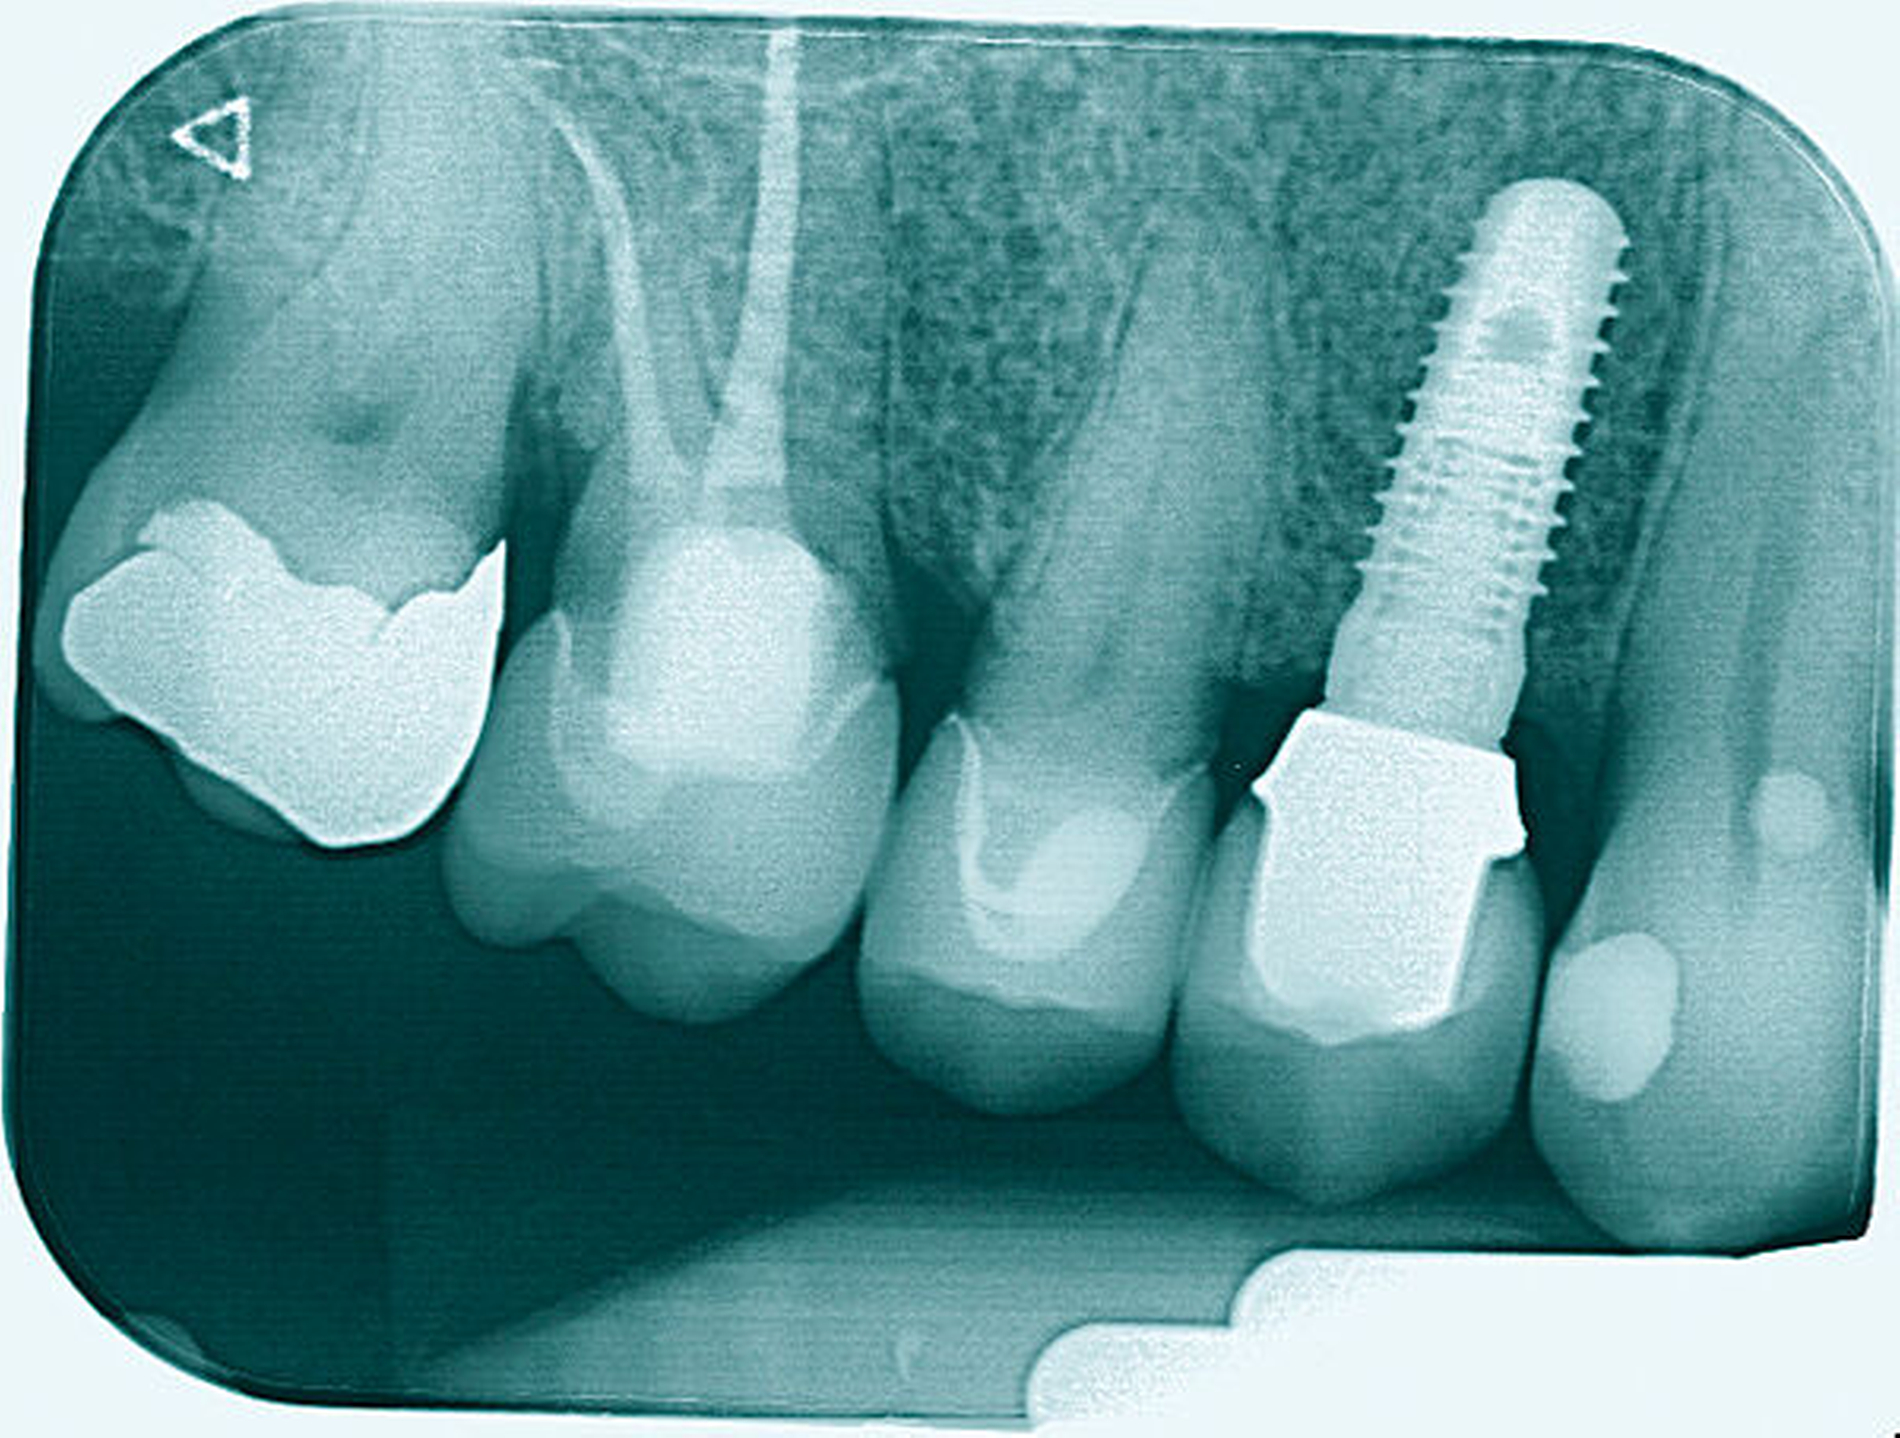

Im Rahmen der Versorgung erfolgte auch ein Austausch der Extensionsbrücke 16–14 durch Einzelkronen auf 16 und 15 sowie einer Implantatversorgung mit Einzelkrone in Regio 014. Der Erhalt des Zahnes 16 ermöglichte so eine wenig invasive Versorgung des ersten Quadranten mit guter Hygienefähigkeit. Alternativ wäre bei Extraktion des Zahnes die Versorgung beispielsweise mit einer ausgedehnten Brückenkonstruktion von 13–17 oder einem weiteren Implantat in Regio 016, vermutlich mit (indirektem) Sinuslift, notwendig gewesen. So konnte der Fall minimalinvasiv zufriedenstellend gelöst werden. Die Patientin ist seit dem Eingriff beschwerdefrei und kommt gut zurecht. Die Situation ist nun seit sechs Jahren stabil.

Eine 53-jährige Patientin stellte sich 2015 mit plötzlich aufgetretenen, starken Beschwerden an Zahn 16 und der Bitte um Abklärung vor. Es erfolgte die klinische und röntgenologische Befundung des Zahnes, der neben einer apikalen Parodontitis auch eine große, fast bis in die Furkation reichende Kronenrandkaries an der mesiobukkalen Wurzel aufwies. Um diesen vorhersagbar versorgen zu können, wurde der Patientin die endodontische Behandlung mit Amputation der mesiobukkalen Wurzel und anschließender Versorgung mittels Vollkrone als Alternative zur Extraktion aufgezeigt. Sie entschied sich für den Zahnerhalt.

So folgte nach der Wurzelfüllung die Amputation der mesiobukkalen Wurzel. Der Zahn wurde nach der Amputation auf Wunsch der Patientin zunächst mit einem Langzeitprovisorium versorgt, das im Verlauf gegen eine definitive Versorgung ausgewechselt wurde. Die Patientin ist seitdem an 16 beschwerdefrei, der Zahn ist stabil und hat eine gute Langzeitprognose.